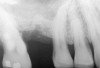

After penetration into the sinus is achieved, a sterile amalgam carrier is used two times to deliver a radiopaque bone substitute into the osteotomy. Then the osteotome used to infracture the subantral floor is lubricated with saline and inserted into the osteotomy until the stop on the osteotome reaches the alveolar crest. This pushes the bone substitute up under the sinus membrane and elevates it. Two more carriers of bone substitute are delivered in the same manner. This will provide around 2 mm of bone height in the sinus (four carriers provide around 2 mm of bone height). A radiograph is then taken to verify that the membrane was elevated, and the bone graft should appear as a dome (Figure 4). If the sinus floor has not been penetrated despite the impression that it was, the bone-graft material may have been pushed laterally. If this occurs, there will be no dome on the radiograph, but, rather, increased osseous density on the lateral aspect of the osteotomy. If this occurs the osteotomy needs to be deepened.

Figure 4  After infracturing the subantral wall with a 3.5-mm osteotome, bone was added and the presence of a dome was confirmed with a radiograph.

Figure 4